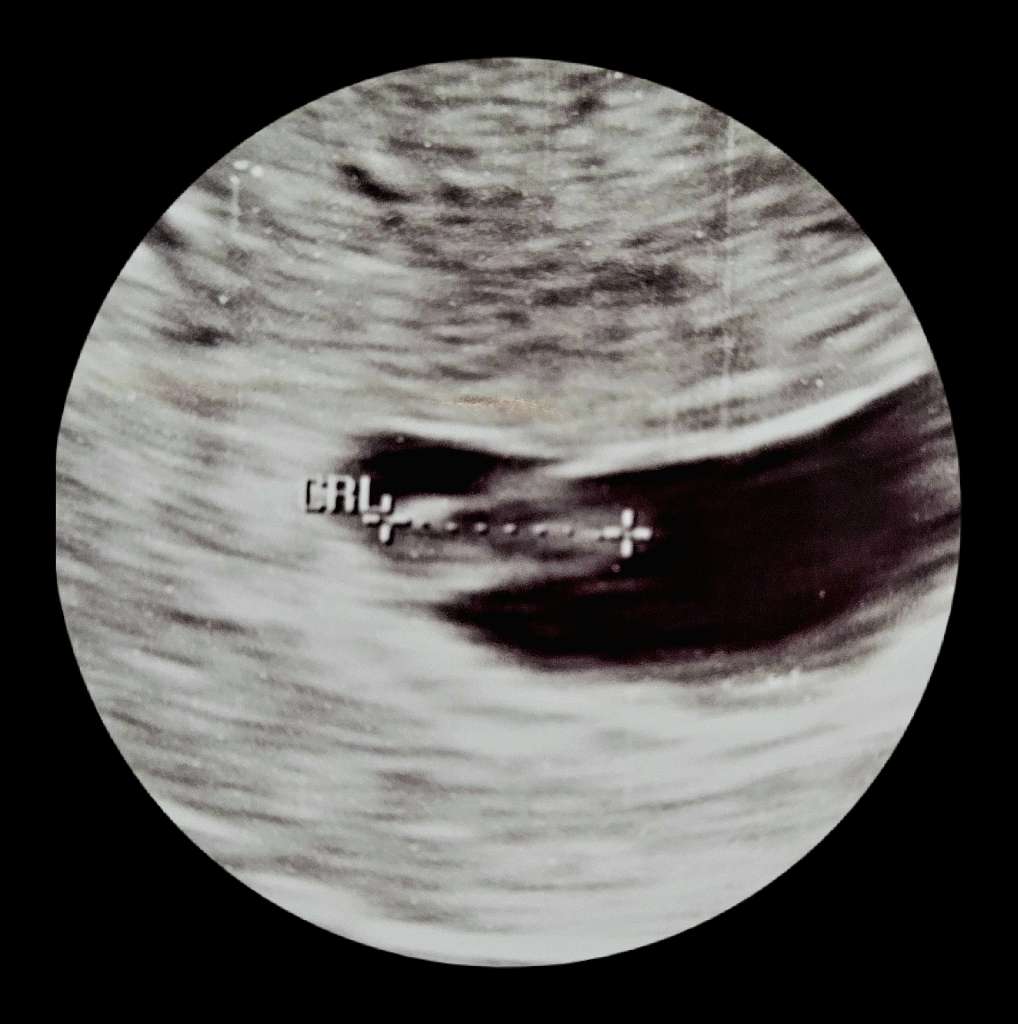

Postanowiłam do Was dołączyć, bo z USG mam termin na 30.01, więc równie dobrze to może być luty.

To jest moja 4 ciąża, ale tylko jedna zakończyła się powodzeniem, po krótce:

Grudzień 2017- poronienie w 5 tygodniu, zabieg łyżeczkowania

Lipiec 2019 - narodziny zdrowej córeczki

Kwiecień 2022 - poronienie zatrzymane w 8 tygodniu, zabieg łyżeczkowania

Maj 2023 - 2 kreski na teście

Mam 36 lat, cykle mam bardzo długie i nieregularne, dlatego opieram się bardziej na wynikach z USG.

Wizytę miałam w środę 14.06, serce bije, 11mm maleństwa.

Trzymam kciuki za powodzenie naszych ciąż